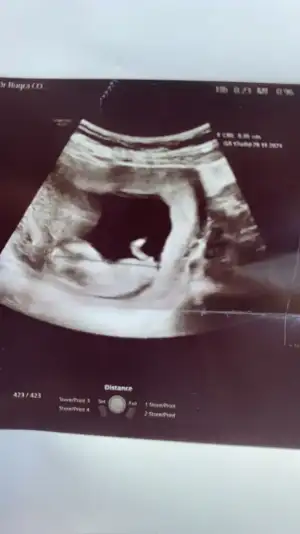

dr soylemeden siz gorun genital nub teorisi ( bebegin cinsiyeti)

Merhaba arkadaslar,aslinda bebegimin cinsiyeti belli,dr.eşime kağıda yazıp verdi ama eşim pazar gunu surpriz yapacagi icin bana søylemiyor,sizin bi tahmininiz varmı?Merakdan çatliyorum.😄😊Eki Görüntüle 2848569

Emin olmadım ama sanki kız gibi geldi bana 🙈 en iyi 11 12 13 haftalar olmalı yada başka USG varsa paylaşın 🤗